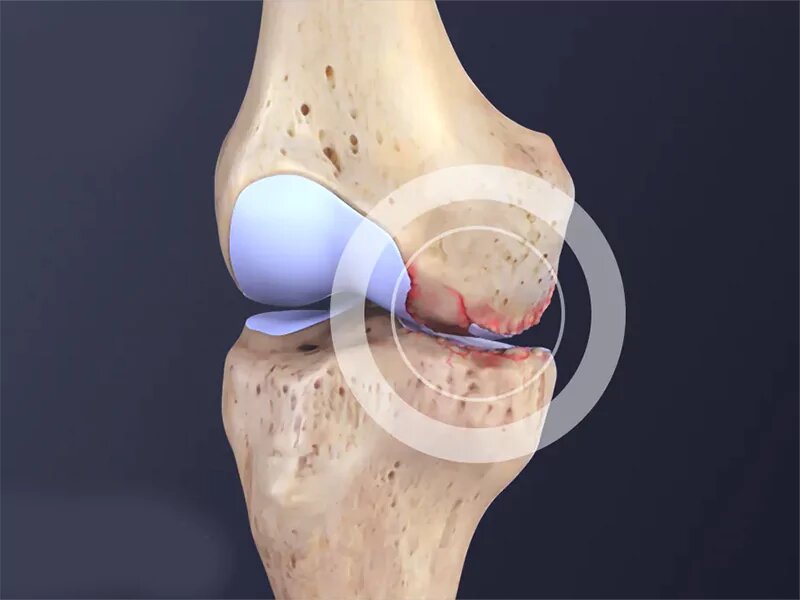

به گزارش خبرگزاری ایمنا، مفصل زانو یکی از پیچیدهترین و پرکاربردترین مفاصل بدن است که از غضروف، استخوان، رباط و مایع سینوویال تشکیل شده است؛ غضروف زانو به عنوان پوشش محافظ استخوانها، وظیفه کاهش اصطکاک و جذب فشار ناشی از حرکات روزمره را دارد و با افزایش سن، این غضروف به مرور نازک میشود و خاصیت ارتجاعی خود را از دست میدهد که زمینهساز آسیبهای جدی از جمله آرتروز میشود و استفاده مداوم از زانو در زندگی روزمره مانند راهرفتن، دویدن یا بالا رفتن از پلهها، این مفصل را در معرض ساییدگی و فرسایش قرار میدهد.

حسین اکبری اقدم، متخصص ارتوپدی و فوق تخصص جراحی زانو و عضو هیئت علمی دانشگاه در گفتوگو با خبرنگار ایمنا با بیان اینکه مفصل از غضروف تشکیل شده است، اظهار کرد: مفصل زانو یکی از مفاصلی است که در زندگی بسیار مورد استفاده قرار میگیرد و با افزایش سن، غضروف مفصل ساییده میشود و فرد دچار آرتروز زانو یا ساییدگی مفصل میشود.

وی با بیان اینکه زمانی که غضروف مفصل زانو از بین برود، فرد دچار آرتروز میشود، افزود: آرتروز زانو دلایل مختلفی دارد که از جمله آنها میتوان به تصادف و ضربه و روماتیسم اشاره کرد؛ به طور کلی، علل بروز آرتروز، علل شناخته شدهای نیست و زمانی که عوامل خطر با یکدیگر ترکیب شود، فرد دچار آرتروز زانو میشود.

متخصص ارتوپدی و فوق تخصص جراحی زانو و عضو هیئت علمی دانشگاه با بیان اینکه درد مهمترین نشانه آرتروز زانو به شمار میرود، تصریح کرد: در ابتدا بیمار هنگام حرکت درد را احساس میکند و پس از آن، در صورت ساییدگی بیشتر غضروف مفصل زانو، بیمار ممکن است درد را حتی هنگام استراحت نیز احساس کند.